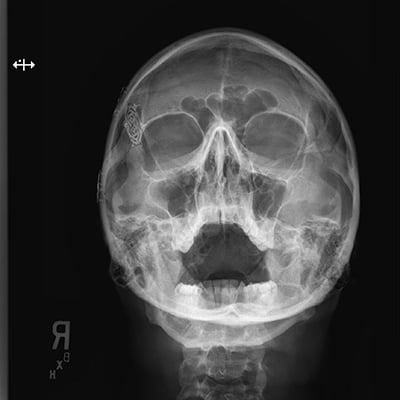

This module will help you achieve optimal images when performing examinations of the skull, facial bones, orbits, and nasal bones. Patient preparation and positioning are discussed, as well as technical settings and patient instructions. Descriptions and images of the expected anatomical structures are included, as well as image evaluation criteria.